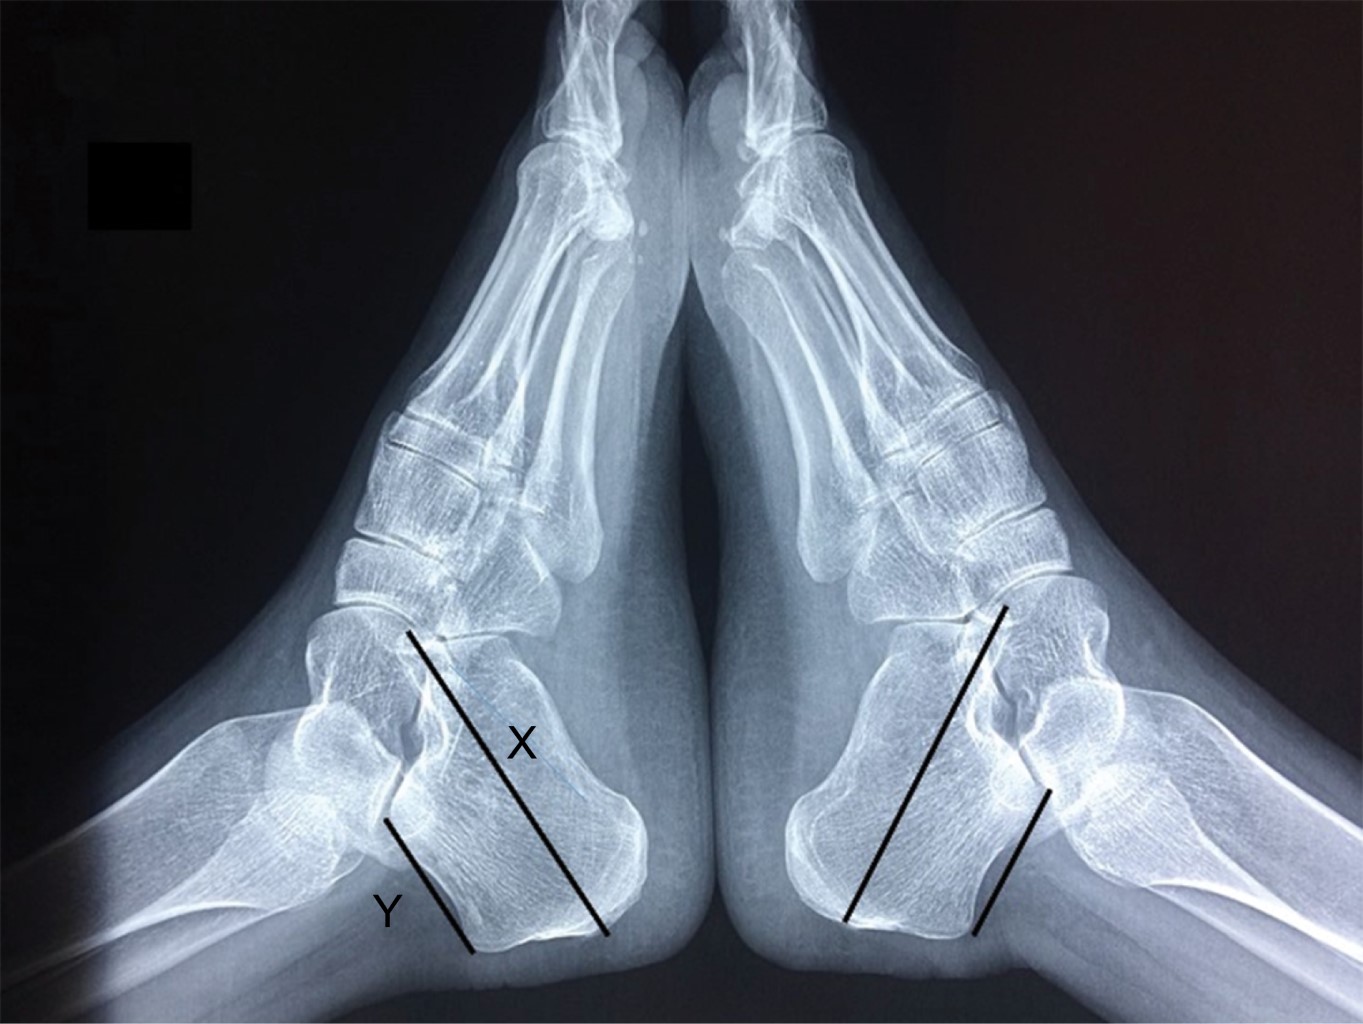

Figure 1